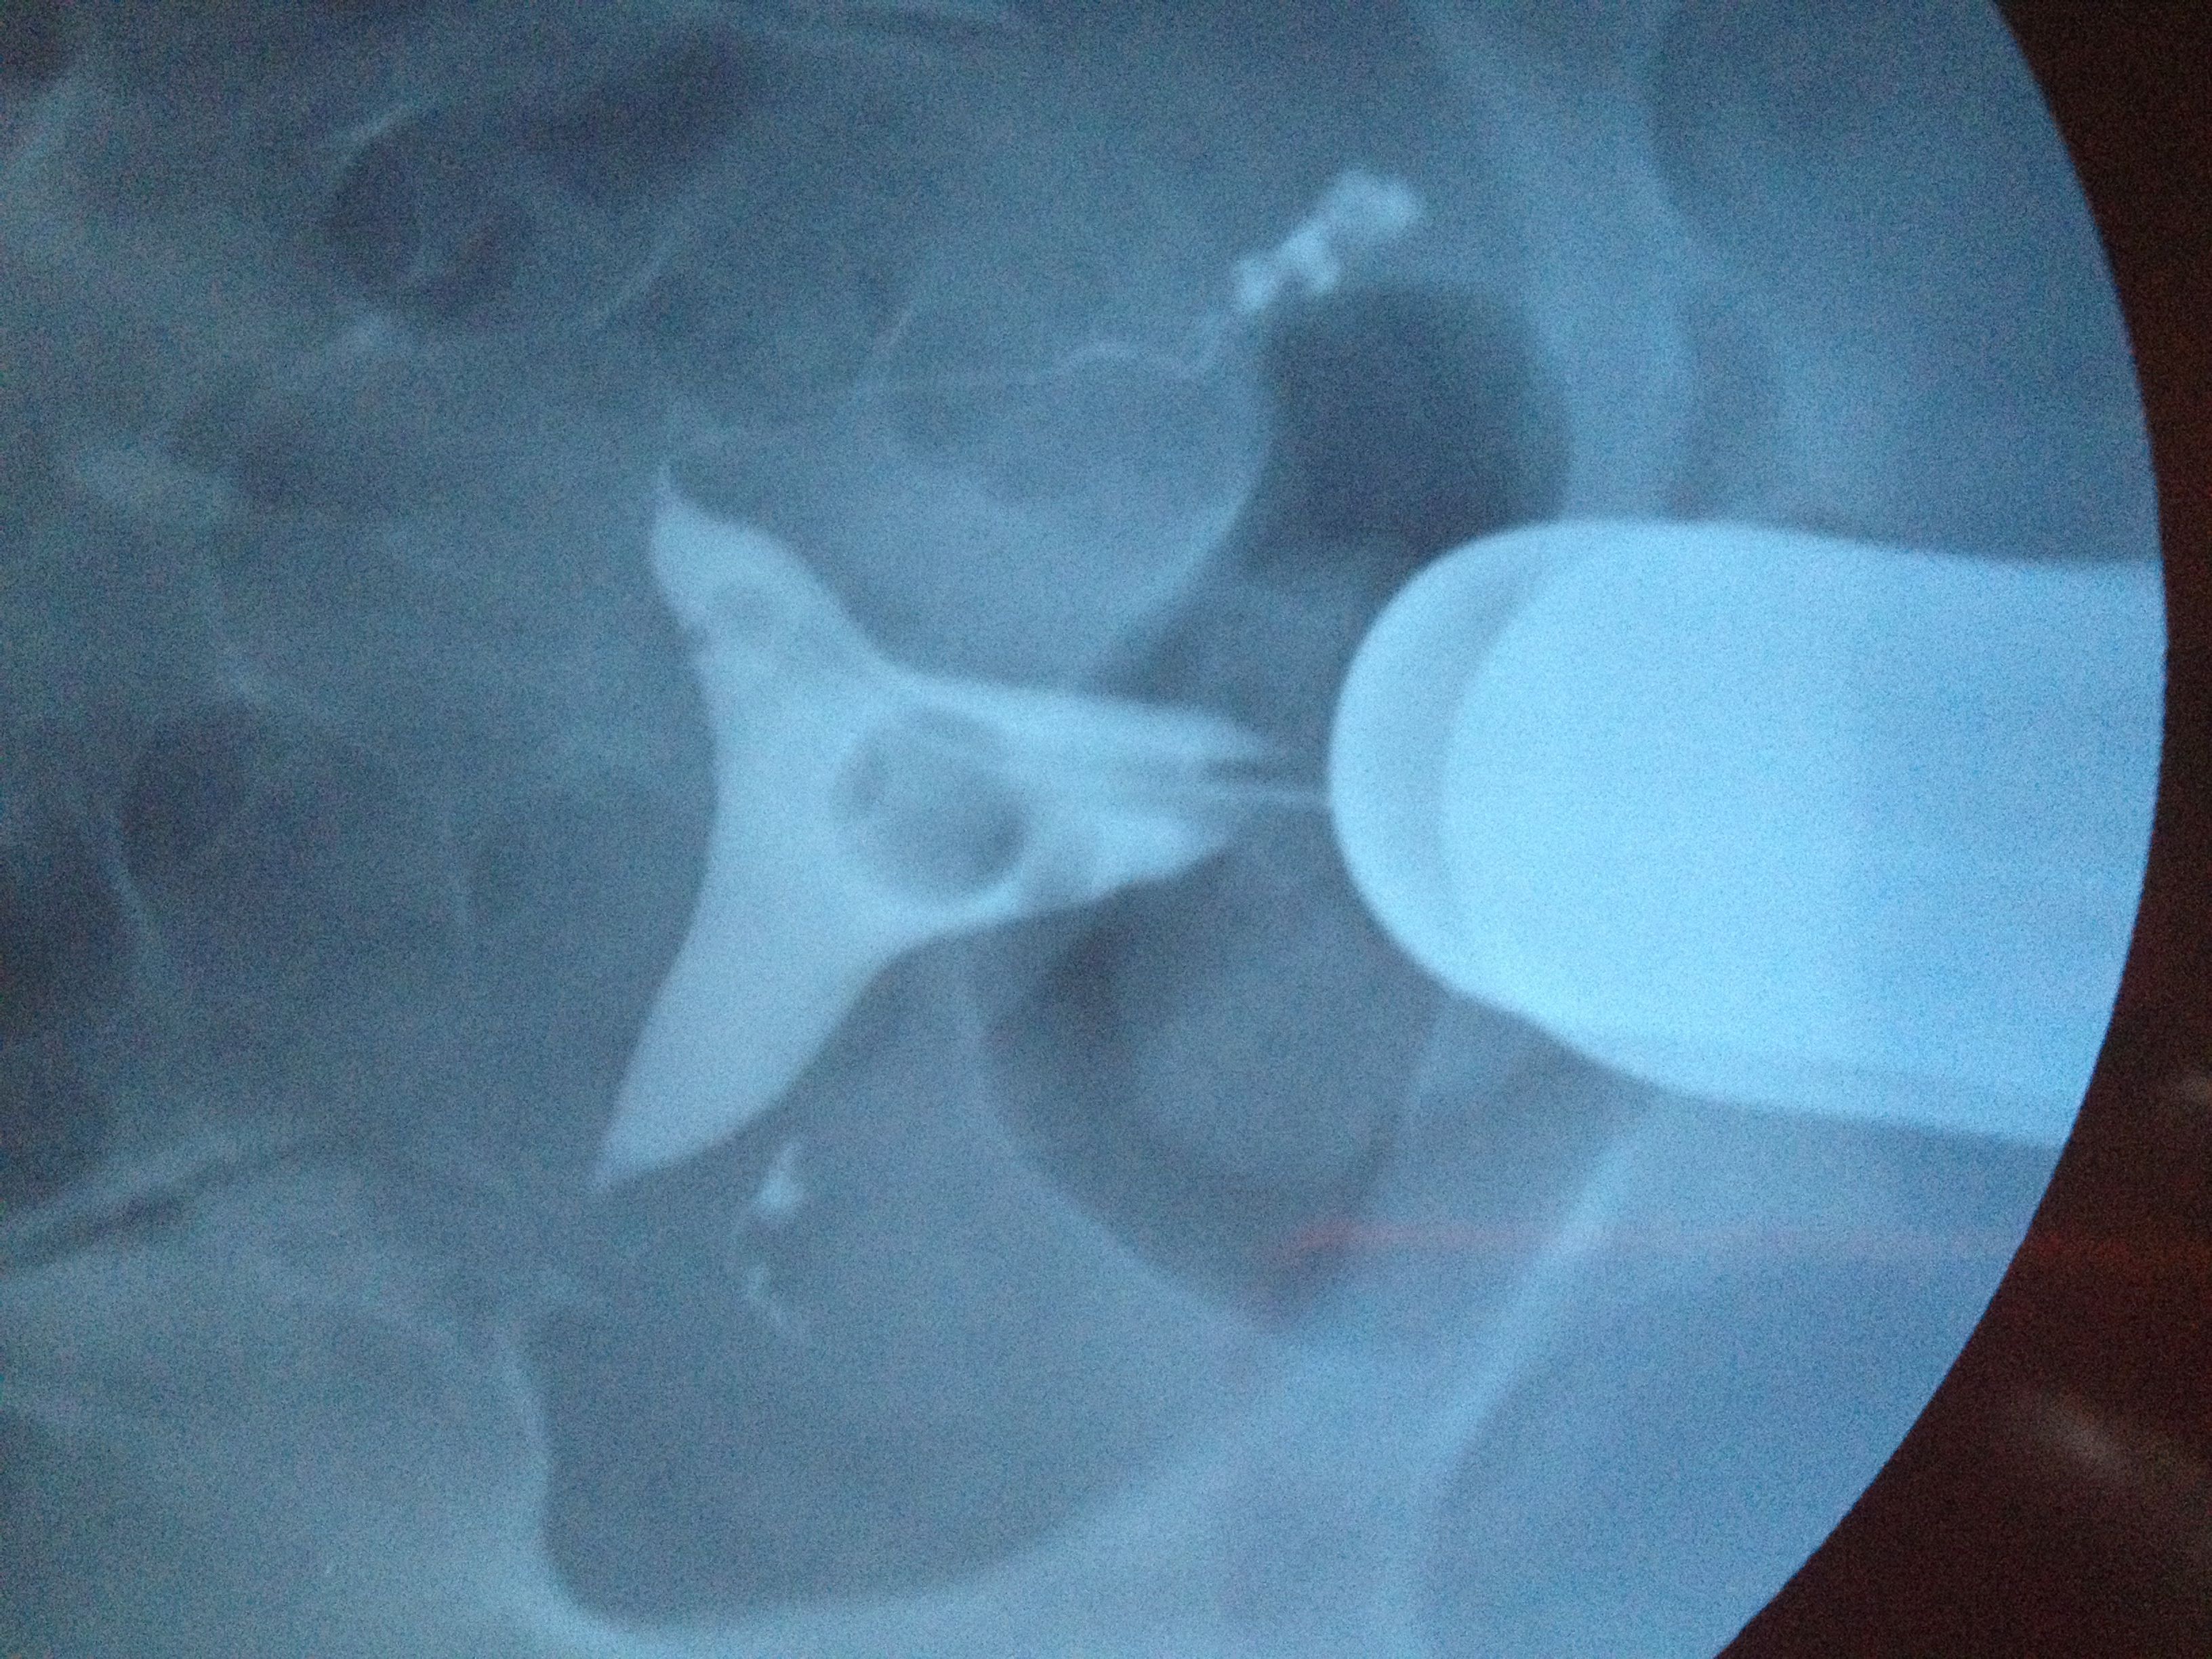

子宫呈鞍形 右侧输卵管走形迂曲 下移 有嵌顿 伞端有照影剂聚集与涌出 左侧走 形略僵直 下移 伞

端有照影剂聚集与涌出 第二次照影盆腔内有等量片状照影剂弥散影响 情况严重吗 应该怎样治疗怀孕呀